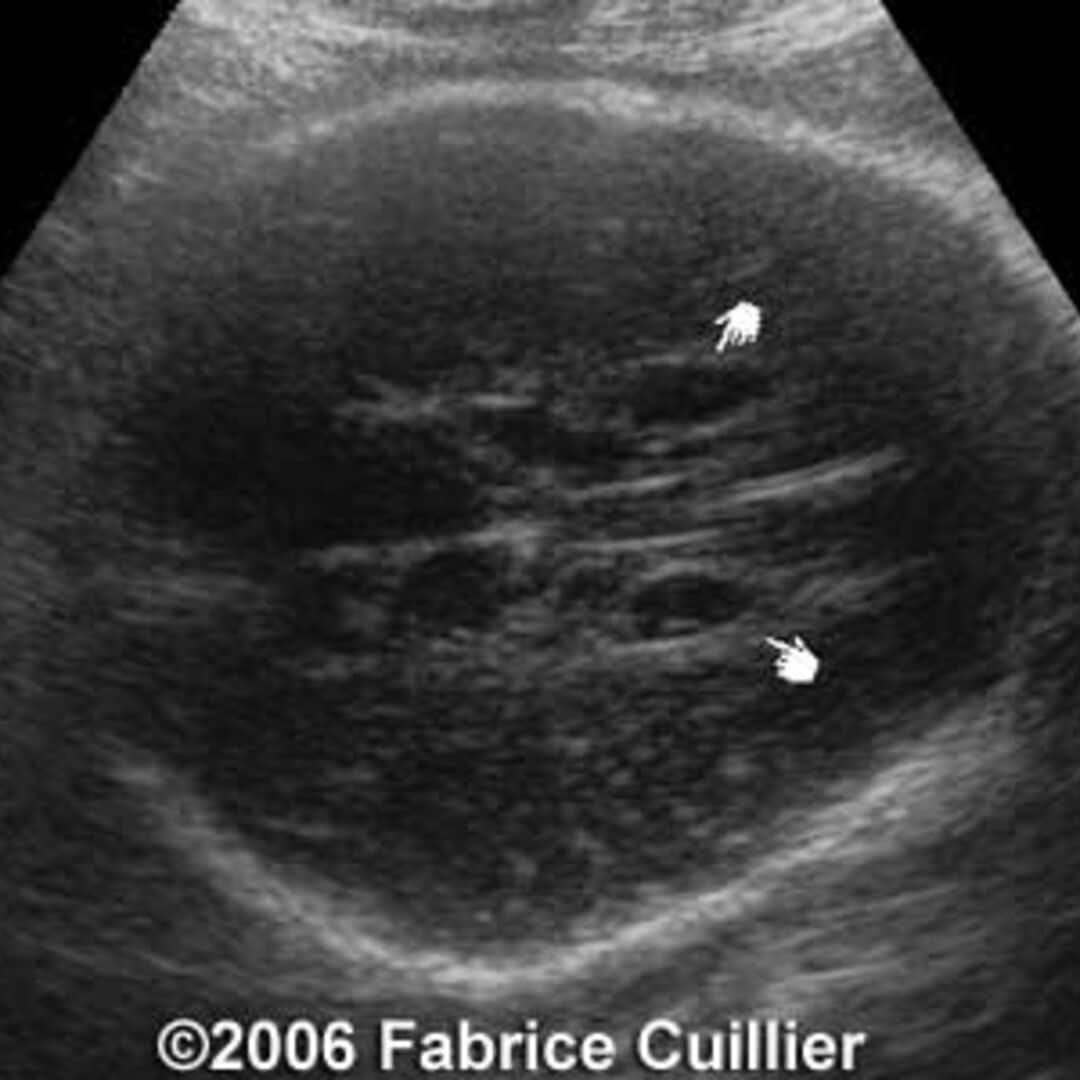

From thefetus.net

📃 Idiopathic subependymal pseudocyst Horn Pseudocyst Definition A pseudocyst is an abnormal collection of tissues and fluids that often develops as a result of leakage from an organ such as the adrenal glands, spleen or. Pseudo horn cysts results from sectioning of a markedly papillomatous skin. True horn cysts represent foci of orthokeratosis within the substance of the lesion, by. So i made a video to explain.. Horn Pseudocyst Definition.